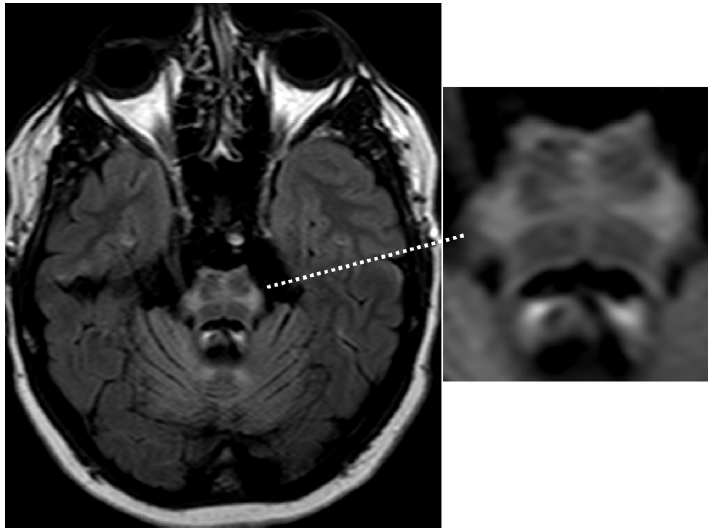

图4显示的是全身免疫疾病相关的小脑萎缩。特异的影像学征象,如T2加权图像中脑干周围的低信号边缘,见于表面铁沉积症(图 5)。

图 5 表面铁沉积症患者表现为小脑性共济失调。头颅MRI T2加权序列图像显示中脑低信号边缘(箭头)。

同时存在小脑性共济失调和自主神经功能障碍的主要原因是多系统萎缩(图 7),典型表现是桥脑出现“十字征”(图 8)。

图7 小脑型多系统萎缩。头颅MRI T1加权序列矢状位图像显示明显的小脑萎缩。

图8 多系统萎缩的“十字征”。图为头颅MRI FLAIR序列图像。十字征高信号是脑桥中缝核和脑桥小脑纤维的神经元丢失所致。